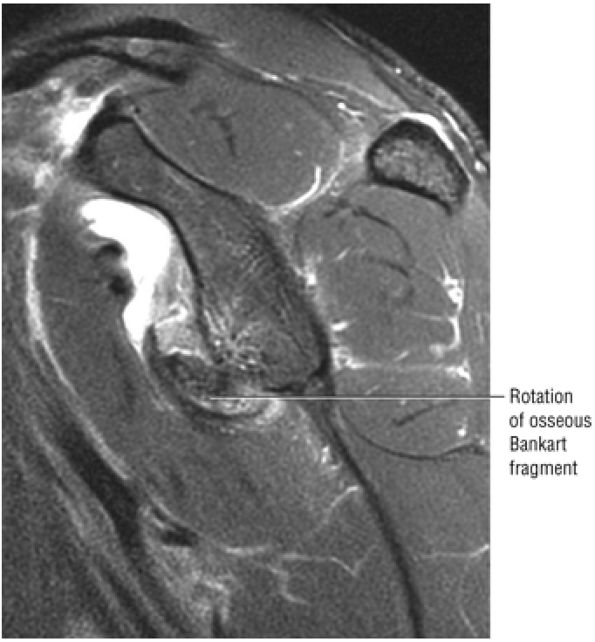

|

![]() |